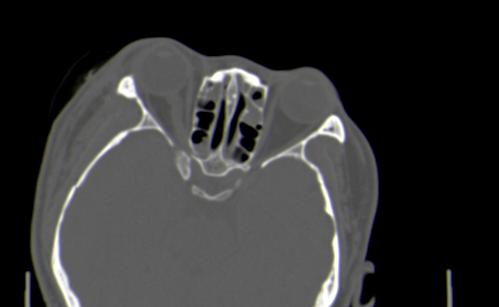

以下是引用皎皎白驹在2006-11-29 8:48:00的发言:[br]影像表现:双侧筛窦和上颌窦、鼻腔内均密度增高,右侧视神经增粗、弯曲,左筛窦顶部筛板及右侧纸板近视神经孔区可见骨折线。[br]结合临床表现考虑:右侧筛窦纸板近视神经孔区骨折致右侧视神经损伤。最好做个眼眶冠状扫描,更明确右侧视神经管是否狭窄。

以下是引用w_jianhua在2006-11-29 10:07:00的发言:[br]影像表现:双侧筛窦和上颌窦、鼻腔内均密度增高,右侧视神经增粗、弯曲,左筛窦顶部筛板及右侧纸板近视神经孔区可见骨折线。[br]结合临床表现考虑:右侧筛窦纸板近视神经孔区骨折致右侧视神经损伤。最好做个眼眶冠状扫描,更明确右侧视神经管是否狭窄。 [br] [br]支持[br]